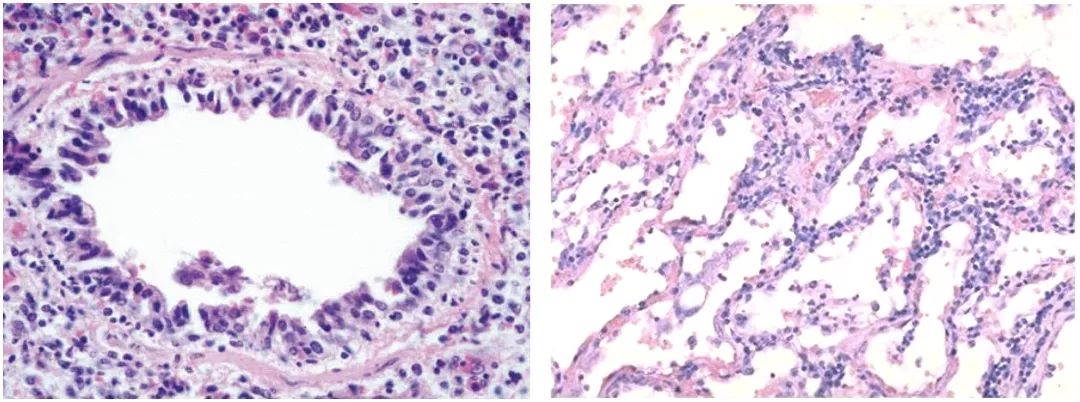

流感病毒主要感染呼吸道上皮,导致呼吸道粘膜坏死脱落【图7】;也可累及肺部,表现为肺泡上皮损伤、肺泡壁毛细血管扩张、淤血,肺泡间隔增宽、淋巴细胞浸润,Ⅱ型肺泡上皮细胞增生【图8】。肺泡腔内炎性渗出、严重者可形成局部或弥漫性的透明膜【图9】。愈合期以间质淋巴细胞浸润和支气管上皮鳞状化生为特征。流感病毒感染通常没有病毒包涵体。机化性肺炎也是流感病毒肺炎的一种表现形式【图10】,此类患者临床上需要加用糖皮质激素治疗。

图7                                                                                                              图8